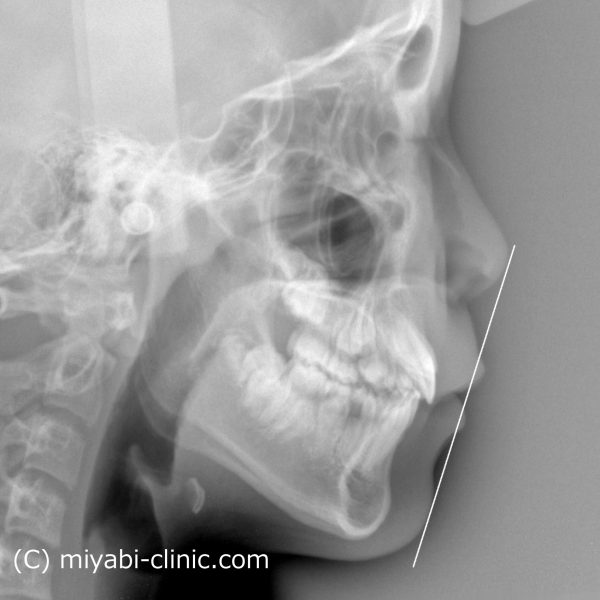

レントゲン写真で確認しても上下の前歯が下がり、

前に飛び出していた上の前歯の傾きが正常化しました。

上下の口唇も下がりました。